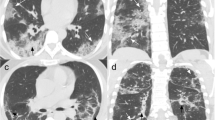

This study included 131 patients who were infected with the Delta variant of COVID-19. After screening, 106 patients with 458 follow-up CT scans were retrospectively selected and divided into complete and incomplete vaccination groups (66 and 40 patients, respectively). Imaging features were automatically extracted, and infection distribution in lung fields and progression pattern tendency were investigated. Furthermore, we extracted the most related clinical and imaging features to establish a vaccination status classification model. An independent testing dataset with 55 patients from another inpatient ward was enrolled to evaluate the generalizability of the model.

The severity of infection in the lung and lung fields of the complete vaccination group was overall lower than those of the incomplete vaccination group. A relatively earlier peak CT abnormality was found on days 8–11 in the complete vaccination group than in the incomplete vaccination group on days 12–15 after the first positive PCR time. The vaccination status classification model achieved the highest performance with an AUC of 0.929 and accuracy of 0.864 in the testing set and an AUC of 0.858 and accuracy of 0.727 in the independent testing set.

In summary, compared to the incomplete vaccination group, the fully vaccinated patients had milder CT abnormalities and earlier peak time for chest impairment. Therefore, the vaccination status is determinable through dynamic imaging and clinical features.